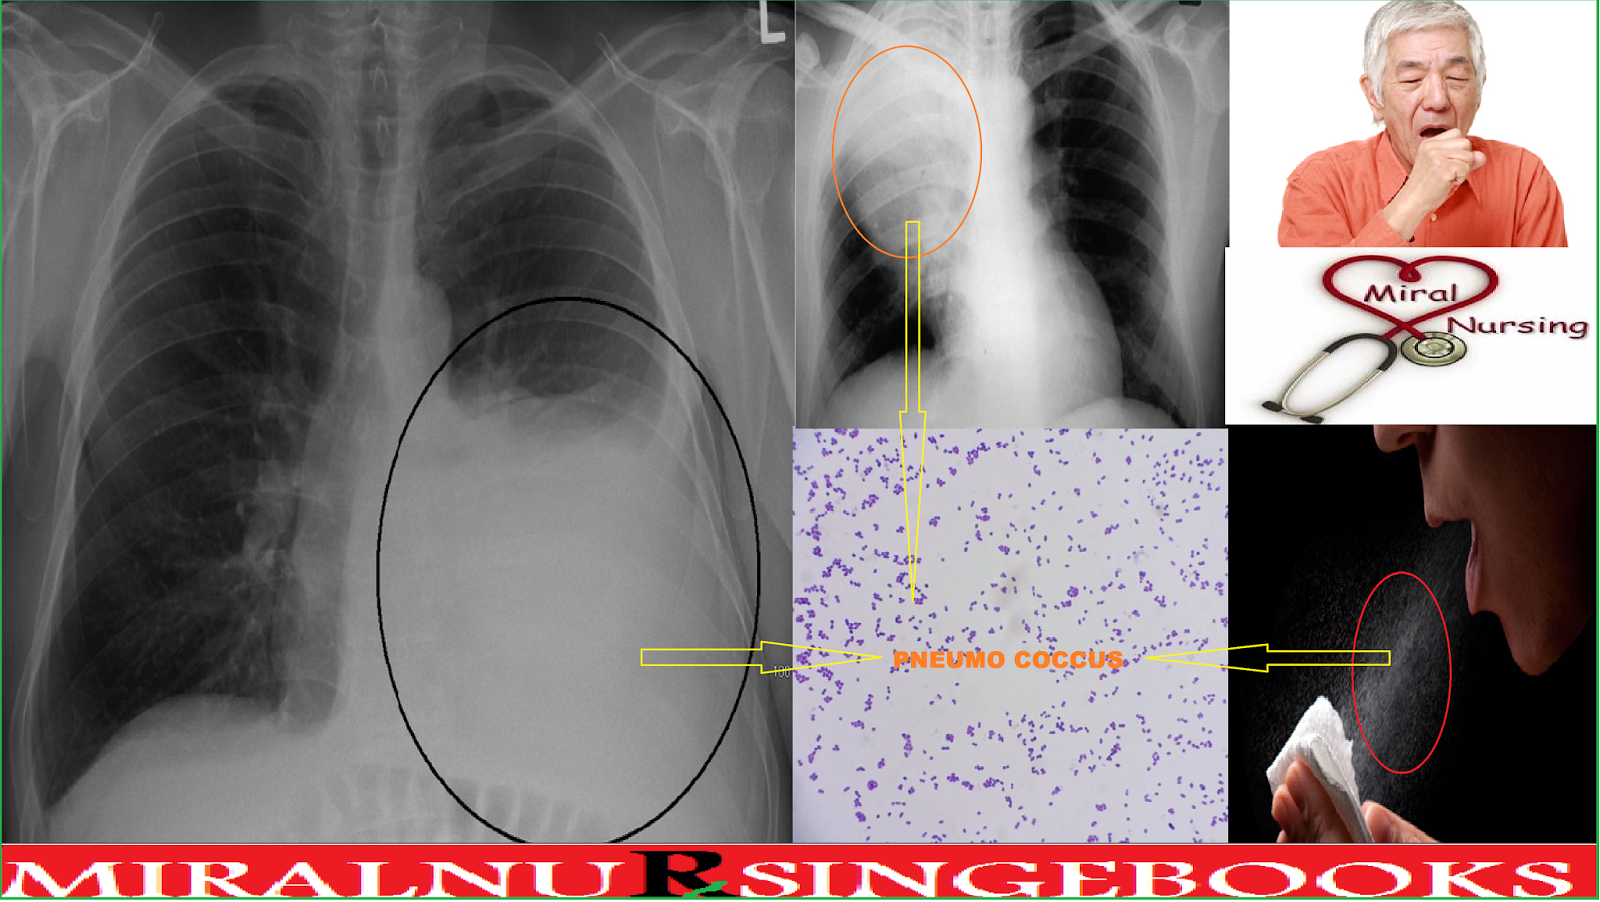

परिभाषा ( INTRODUCTION ) - निमोनिया एक फेफड़ो का संक्रमण हैं

निमोनिया में फेफड़ों के पैरेन्काइमा में सिकुड़न से सूजन आती हैनिमोनिया वायुकोशीय रिक्त स्थान ( ALVEOLAR SPACES ) और फेफड़ों के समेकन से सूजन है जो अंतरालीय ऊतक के रिसाव से होता हैं

बच्चों में निमोनिया का 90 % कारण PNEUMO COCCUS बैक्टीरिया से होता हैं

- चेस्ट एक्स-रे